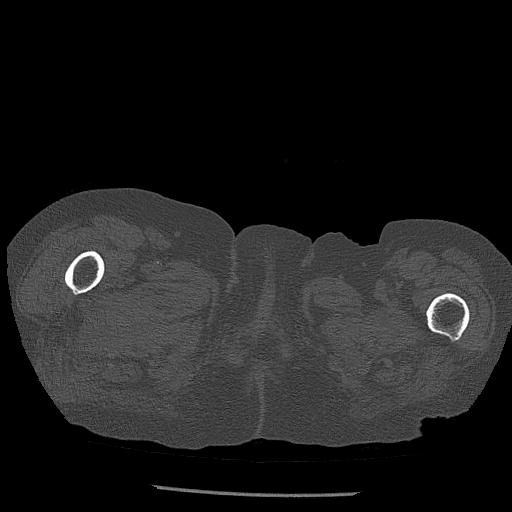

100703 1/27 両股正面+軸 1/29 両股正面+軸 94歳女性 パンソンロン